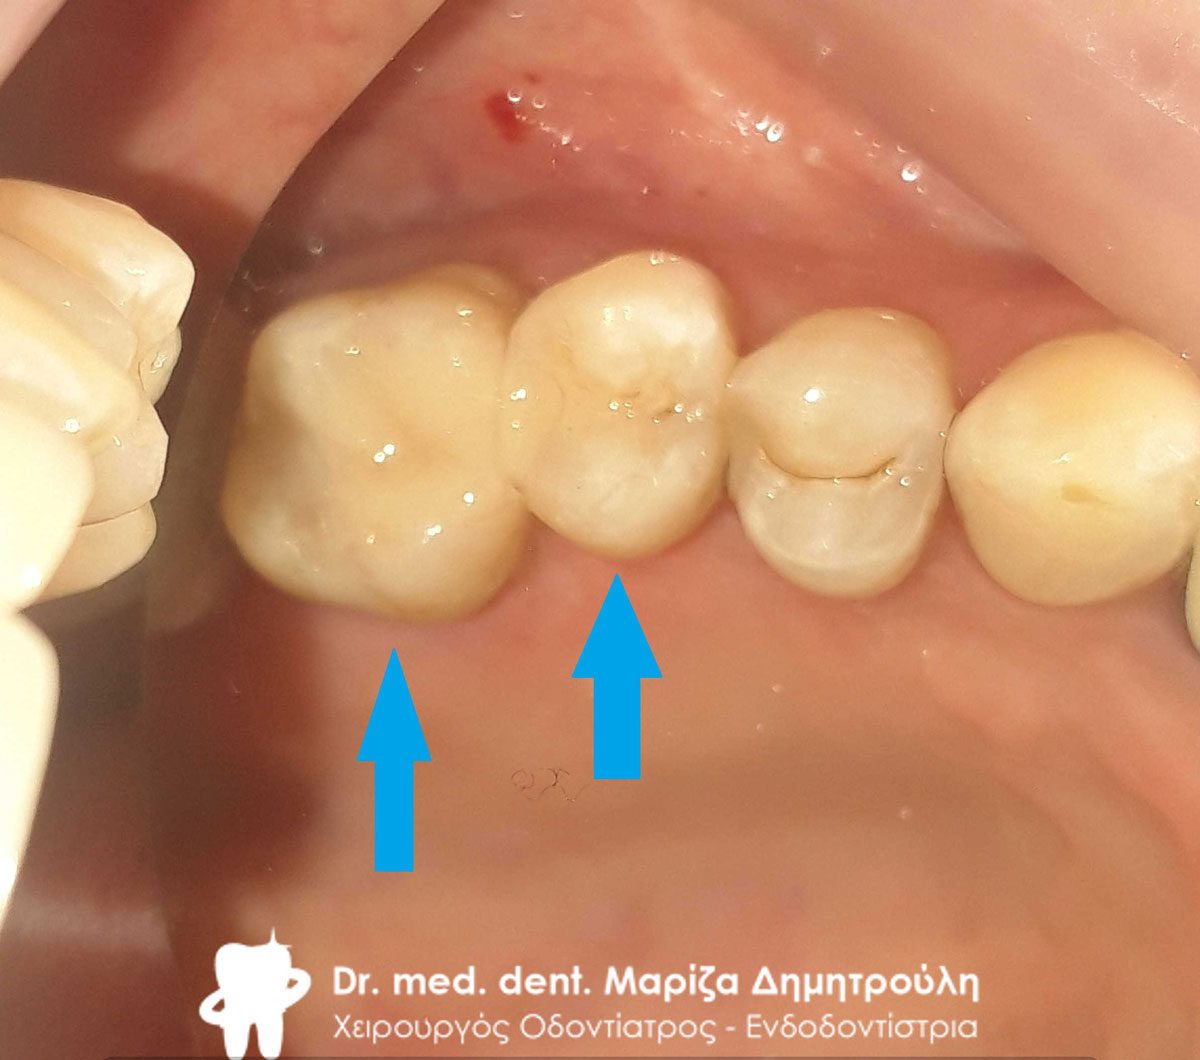

Εικόνα των τροχισμένων δοντιών με τις απαιτούμενες ανασυστάσεις

Εικόνα των τροχισμένων δοντιών με τις απαιτούμενες ανασυστάσεις